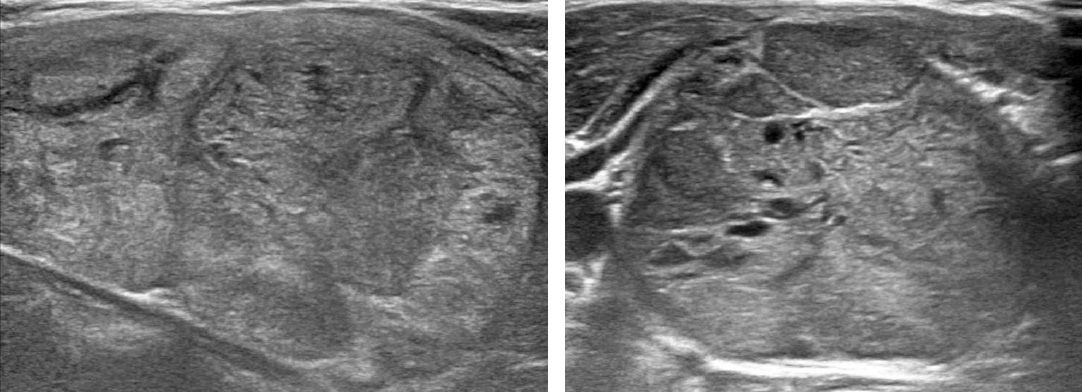

Small lumps or growths on the thyroid gland are usually benign and cause no symptoms. A small percentage of these thyroid nodules, however, are malignant. Physicians use high-resolution ultrasonography1 to diagnose thyroid nodules, following up with a biopsy for nodules that exhibit common signs of malignancy; these include solidity, irregular margins, microcalcifications, and a shape that is taller than it is wide (Figure 1).

Figure 1. Ultrasonography images of a benign nodule (left) and a malignant nodule (right).